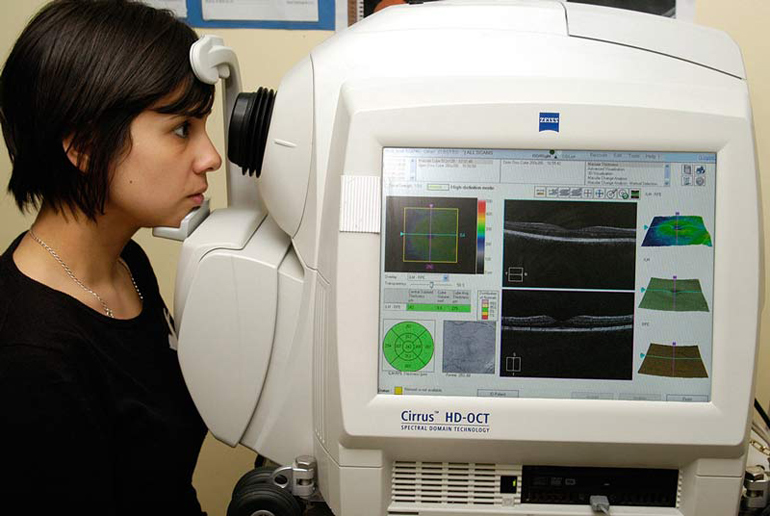

Диагностика зрения: Когерентная томография сетчатки